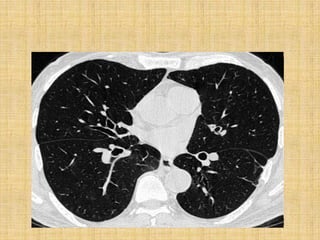

•In an isolated lung, the

smallest bronchi visible

(arrows) measures 2 to 3 mm

in diameter.

• Bronchi and bronchioles are

not visible within the

peripheral 1 cm of lung.

• Artery branches that

The diameters of vessels and bronchi are approximately equal.

The outer walls of bronchi and vessels are smooth and sharp.

Bronchi are invisible within the peripheral 2 cm of lung